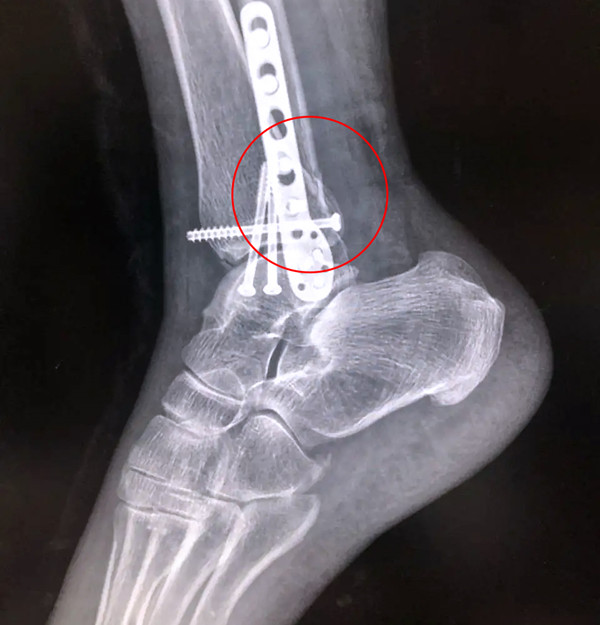

【醫療科普】Pilon骨折

有一種特殊類型的踝關節骨折,可能在X影像平片上就不能顯示出來,它就是脛骨的關節面往里塌陷,我們又稱之為叫“Pilon骨折”。當它往里塌陷后,我們在X影像平片上可能看不出來它是否塌陷,但是我們在CT上可以360°看到踝關節的影像,這樣就可以看出患者是否存在踝關節塌陷的骨折。同樣道理,我們在做Pilon骨折手術的時候,普通二維的X影像并不能判斷我們手術復位情況的好壞,這個時候如果醫生手上有能夠照三維影像的工具,那么對于醫生的準確手術是非常有好處的。